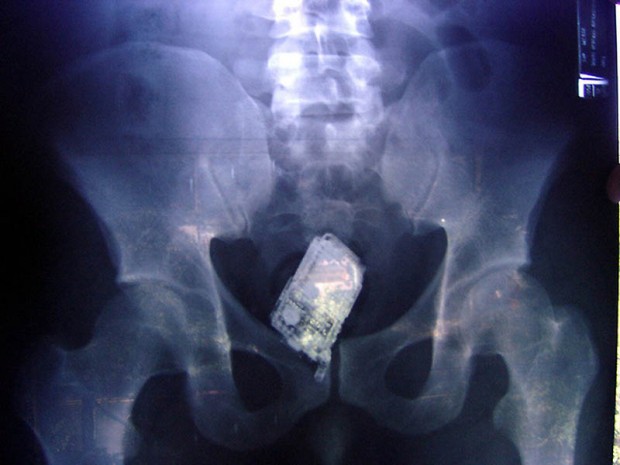

14. Мобильник в кишечнике заключенного.